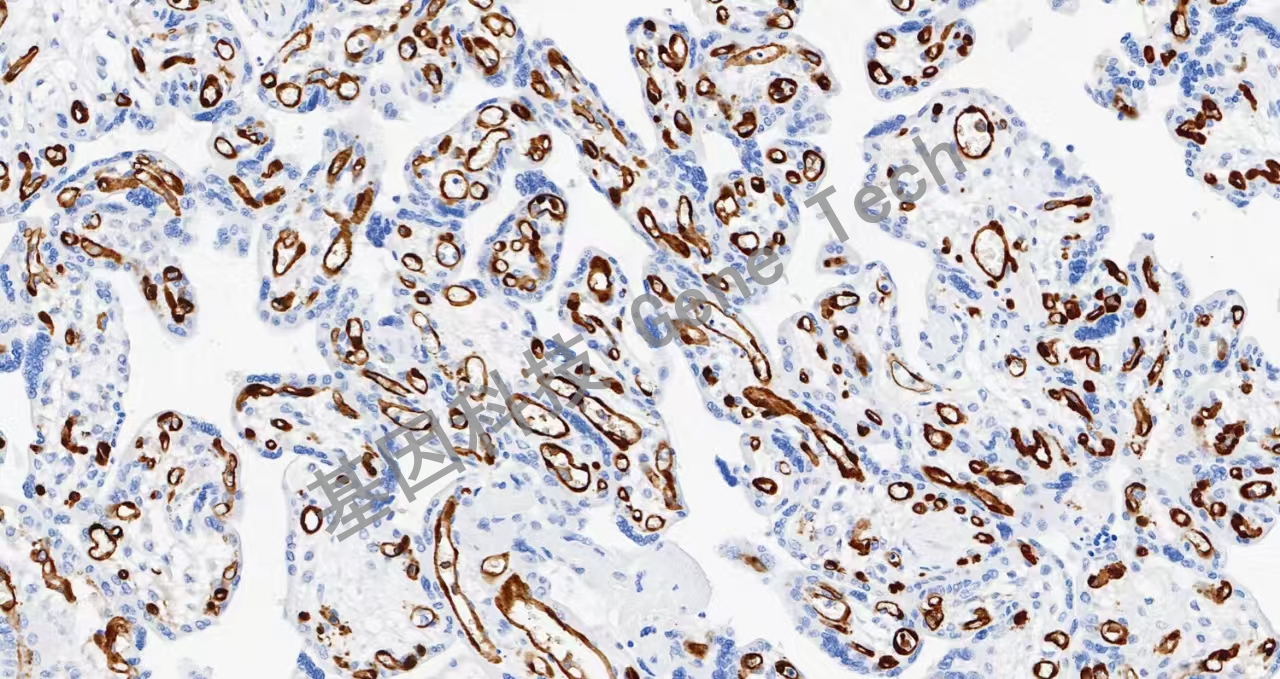

| 胎盤石蠟切片,用 IDO1(GT2296)染色,細(xì)胞漿/細(xì)胞核陽(yáng)性,DAB 顯色。 | ||

| 預(yù)處理:高pH熱修復(fù) | 陽(yáng)性部位:細(xì)胞漿/細(xì)胞核 | 陽(yáng)性對(duì)照:扁桃體 |

| 簡(jiǎn)介:IDO1(吲哚胺2,3-雙加氧酶)是一種含血紅素的酶,在許多組織和細(xì)胞中生理表達(dá),如小腸、肺、胎盤。IDO1是免疫系統(tǒng)的重要組成部分,在對(duì)抗各種病原體的自然防御中發(fā)揮作用。它通過在樹突狀細(xì)胞、單核細(xì)胞和巨噬細(xì)胞中表達(dá),調(diào)節(jié)T細(xì)胞的行為。最近的研究表明,IDO1在腫瘤發(fā)展過程中被激活,幫助惡性細(xì)胞逃脫免疫系統(tǒng)的根除。IDO1在多種類型的癌癥中表達(dá),如卵巢癌、結(jié)腸癌等。 | ||